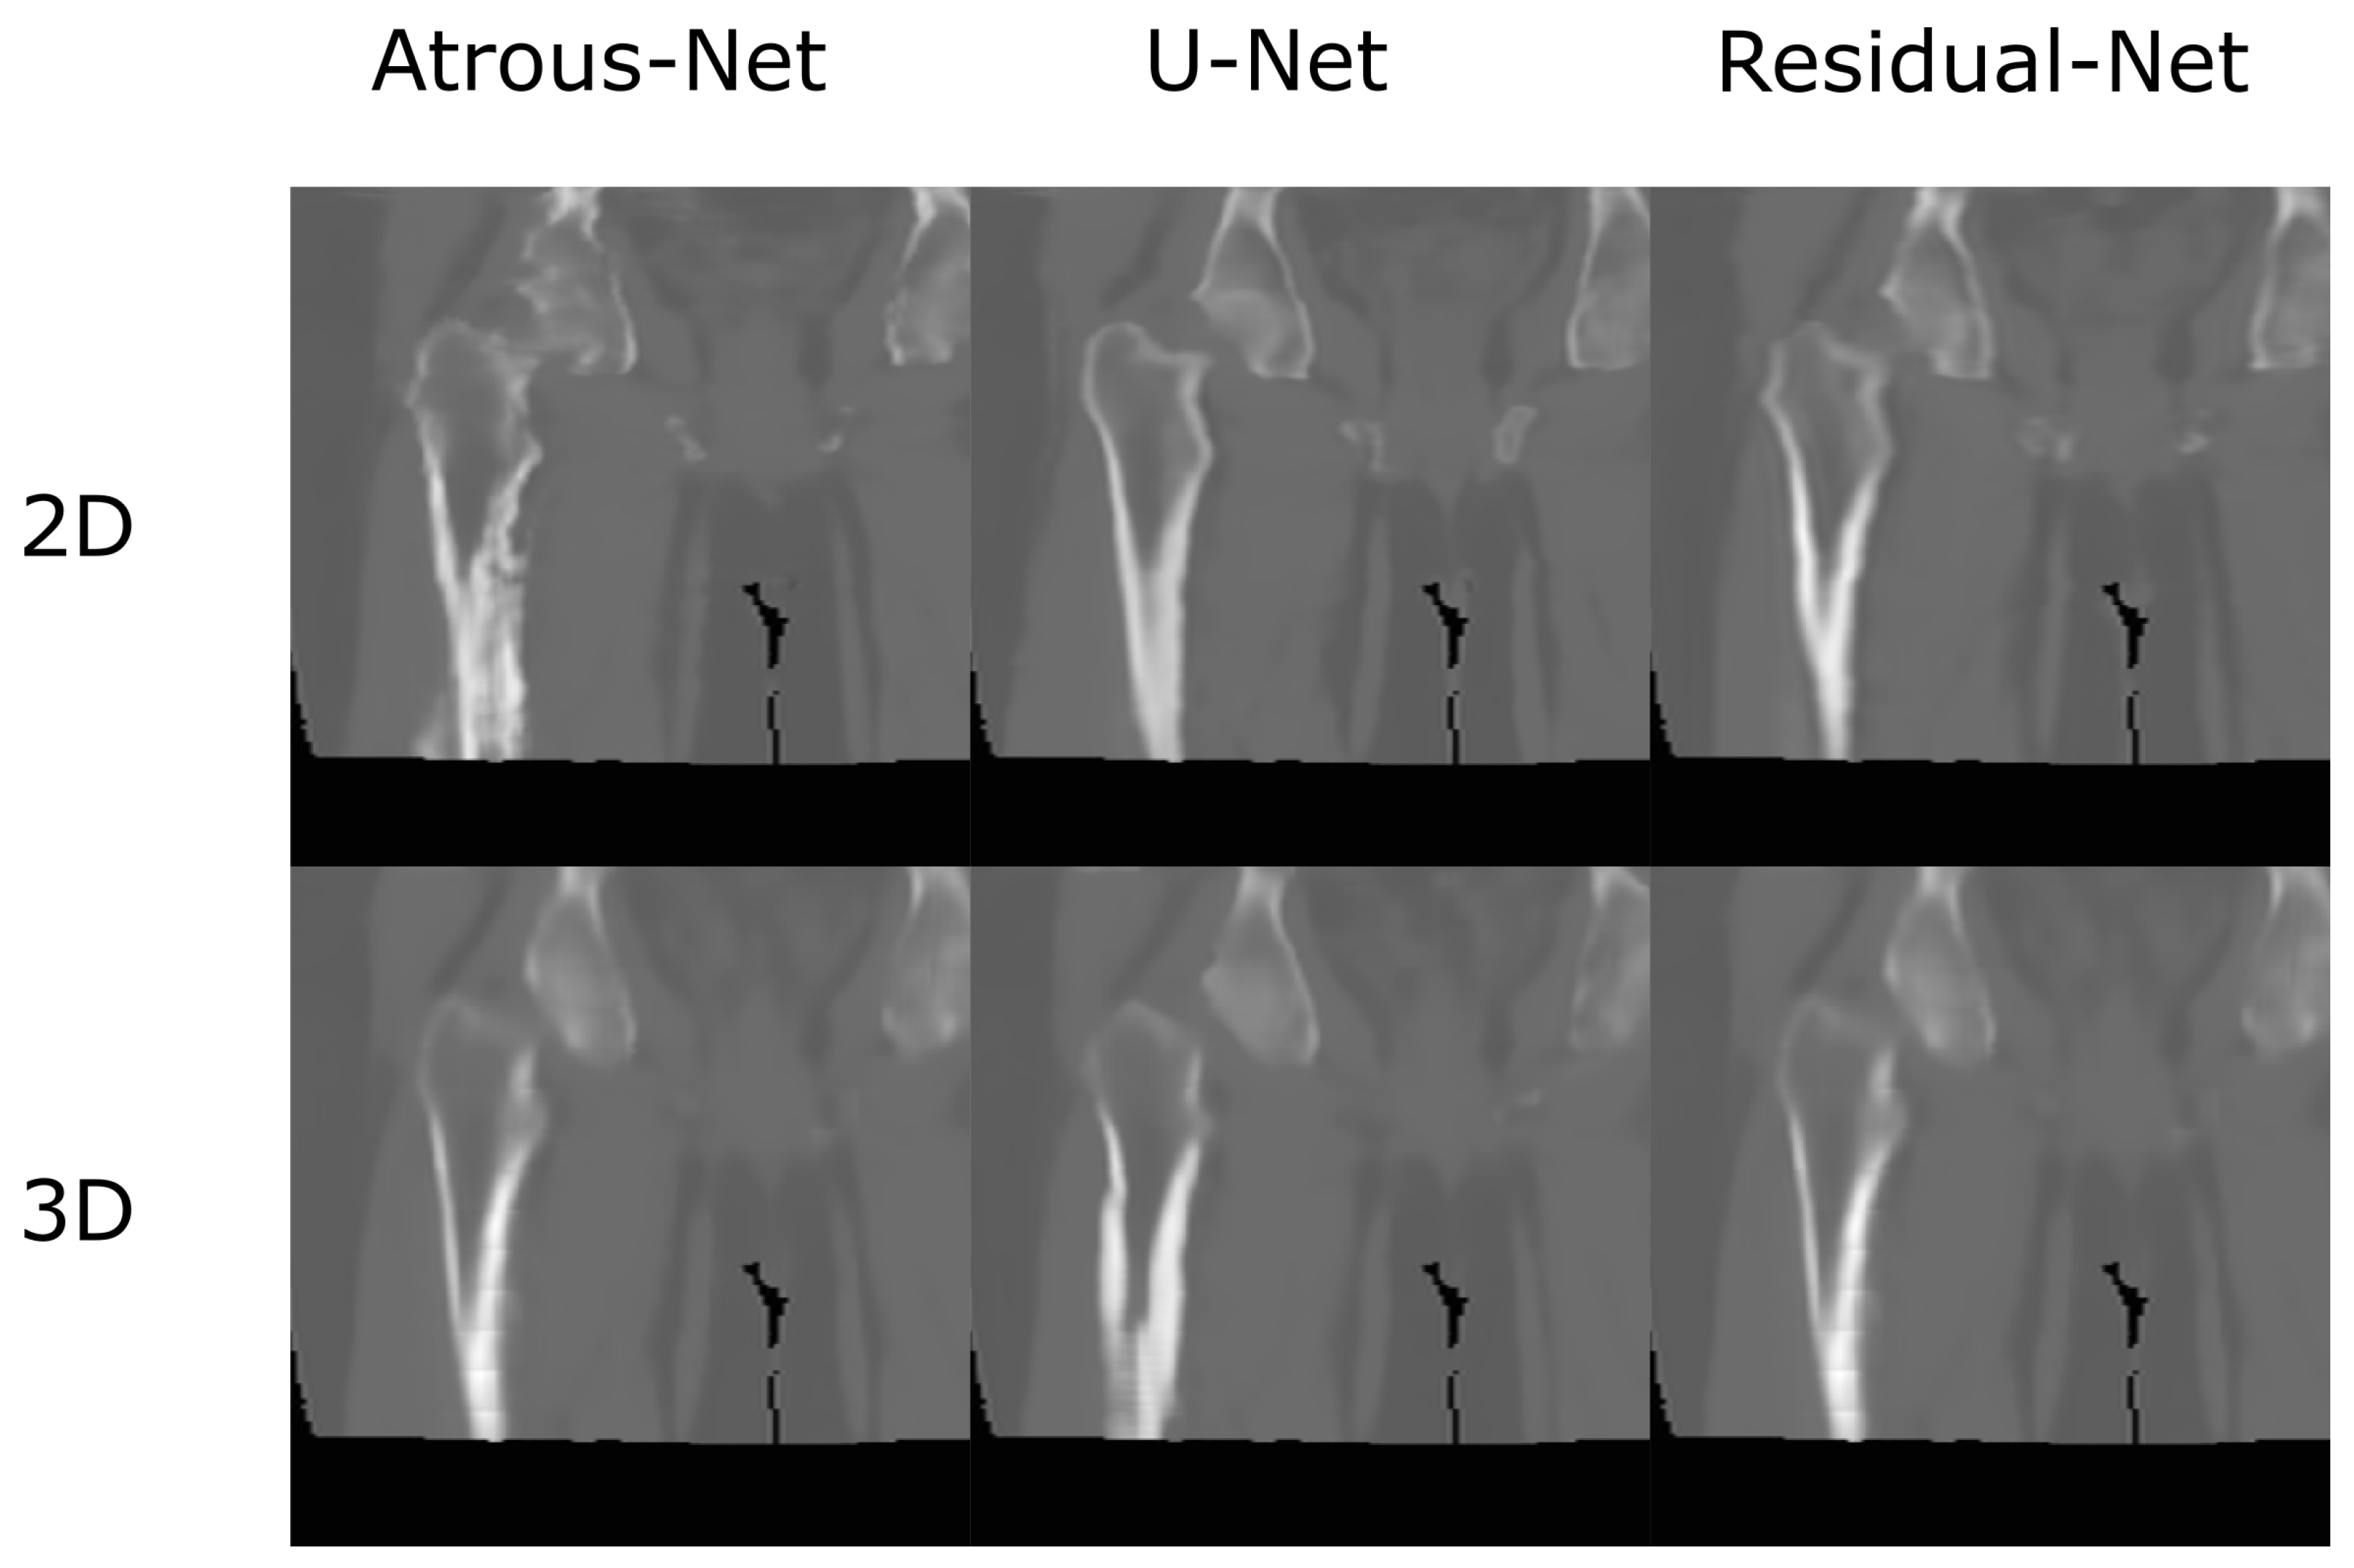

3.1. Head Dataset Results

The results for all tissues using the head dataset are depicted in Table 1, Table 2 and Table 3; the results using only the bone voxels are detailed in Table 4, Table 5 and Table 6; the results using only the fat voxels are detailed in Table 7, Table 8 and Table 9; and the results using only the soft-tissue voxels are detailed in Table 10, Table 11 and Table 12. The best performing 2D network for the head dataset was the Residual-net. The results presented a MAE of 99.83 HU, a PSNR of 24.83 and a Pearson Coefficient of 0.931 in all tissues, and a MAE of 326.33 HU, a PSNR of 19.04 and a Pearson Coefficient of 0.826 in bone voxels. The ANOVA test revealed a statistically significant effect of the 2D architectures for MAE results (all tissues: F 2 , 36 = 91.1 , p < 0.001 ; bone: F 2 , 36 = 74.2 , p < 0.001 ) and PSNR results (all tissues: F 2 , 36 = 99.3, p < 0.001 ; bone: F 2 , 36 = 85.6, p < 0.001 ). A paired t-test was used to compare the Residual-net to the other networks reporting also statistically significant differences in the MAE and in the PSNR (Table 13). Using 2D convolutions, the Atrous-net and the U-net performed 5% and 18% worse than the residual-net, respectively. Moreover, the U-net network was clearly behind the other networks using 2D convolutions. Nevertheless, the U-net in 3D-16 obtained a MAE of 89.54 HU, a PSNR of 25.69 and a Pearson Coefficient of 0.943 in all tissues, and a MAE of 289.10 HU, a PSNR of 20.05 and a Pearson Coefficient of 0.861 in bone voxels, which were the best results for the head dataset. The ANOVA test also reported a statistically significant effect of the 3D networks for the MAE (all tissues: F 2 , 36 = 63.2 , p < 0.001 ; bone F 2 , 36 = 189.8 , p < 0.001 ) and the PSNR (all tissues: F 2 , 36 = 10.5 , p < 0.001 ; bone: F 2 , 36 = 83.1 , p < 0.001 ). The post hoc paired t-test that is depicted in Table 14 also reported statistically significant differences in the MAE and PSNR after comparing each architecture. Summarizing, the results using 3D convolutions from the U-net were 17% and 10% better than those of the Atrous-net and Residual-net, respectively. Visual result examples of head pseudo-CTs are depicted in Figure 6 and Figure 7. Table 15 shows the time needed to synthesize a whole head volume using the different architectures.

Figure 6. Head results using 2D networks.

Applsci 12 11600 g006

Figure 7. Head results using 3D-16 networks.

Applsci 12 11600 g007